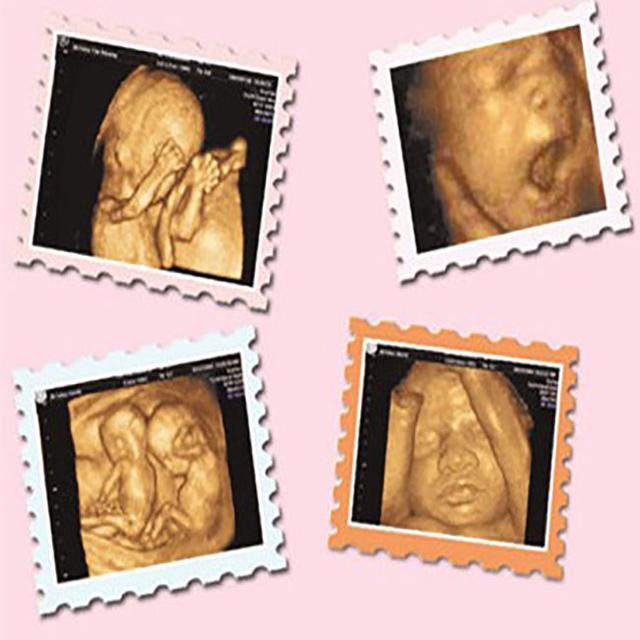

呵呵 , 这个问题确定不是在问我吗?我记得当初在怀孕26周时 , 为了做大四维排畸检查一次过 , 我特地吃过早餐 , 走半小时的路去医院 , 再排队半小时 , 才轮到我进去做检查 , 没有想到胎宝宝就是不配合 , 医生说 , 宝宝在肚子里趴着 , 看不到正面 , 大概十几分钟过去了 , 宝宝还是不愿意动 , 医生只好跟我说 , 出去走走再回来 , 也许宝宝就翻转过来了 , 我去了附近公园 , 转悠差不多一小时才回到医院复查 , 宝宝依旧懒洋洋的趴着不动 , 很无奈

医生只好再次叮嘱我两周后 , 再来复查 , 两周过后 , 我再来复查了 , 宝宝这一次翻转过来了 , 有趣的是 , 这一次依旧看不完整 , 原因是这次宝宝居然双手捂住脸 , 是的 , 看不见宝宝的正面 , 医生没办法 , 只好拍其他角度 , 听多了很多宝宝有裂唇 , 看不到正面 , 我不放心 , 在孕30周 , 我又去医院检查 , 这一次没再拍四维彩超了 , 医生给我做了个系统B超 , 结果说没问题 , 我才放心 。